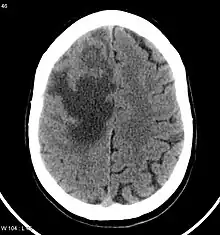

CNS metastases are diagnosed through imaging techniques that produce detailed images of the inside of the body, including parts such as the bones, organs, muscles, and nerves.[13] Magnetic resonance imaging (MRI) and computed tomography (CT) are two representative imaging procedures for this purpose.[12]

MRI scans use strong magnetic fields and radio waves to create an image, while CT scans use X-rays. MRI scans produce more detailed images of bodily structures, particularly soft tissues including the brain,[13] and are better at detecting CNS metastases than CT scans. However, CT scans are sometimes used for the initial imaging modality due to their lower cost and efficiency in screening for multiple conditions.[14]